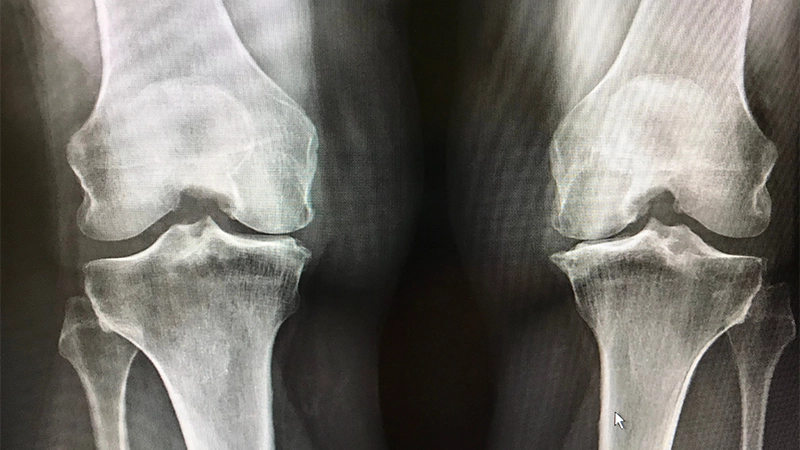

Knee Osteoarthritis

Joint Calcification- It is one of the most common joint disorders. The cartilage in the knee joint wears down, the bones begin to rub against each other and symptoms such as pain, stiffness and restricted movement occur.

Although this condition is usually associated with the aging process, sports injuries and overload can also trigger knee arthritis. Treatment of knee arthritis is aimed at relieving pain, reducing inflammation and maintaining joint mobility. Physical therapy, exercise, weight control and, in some cases, surgical interventions are among the methods frequently used in the management of knee arthritis. Intra-articular injections and painkillers can also help relieve symptoms.

The diagnosis is made using physical examination, medical history and imaging methods (such as X-ray, MRI). Laboratory tests can also be used to rule out other joint diseases.